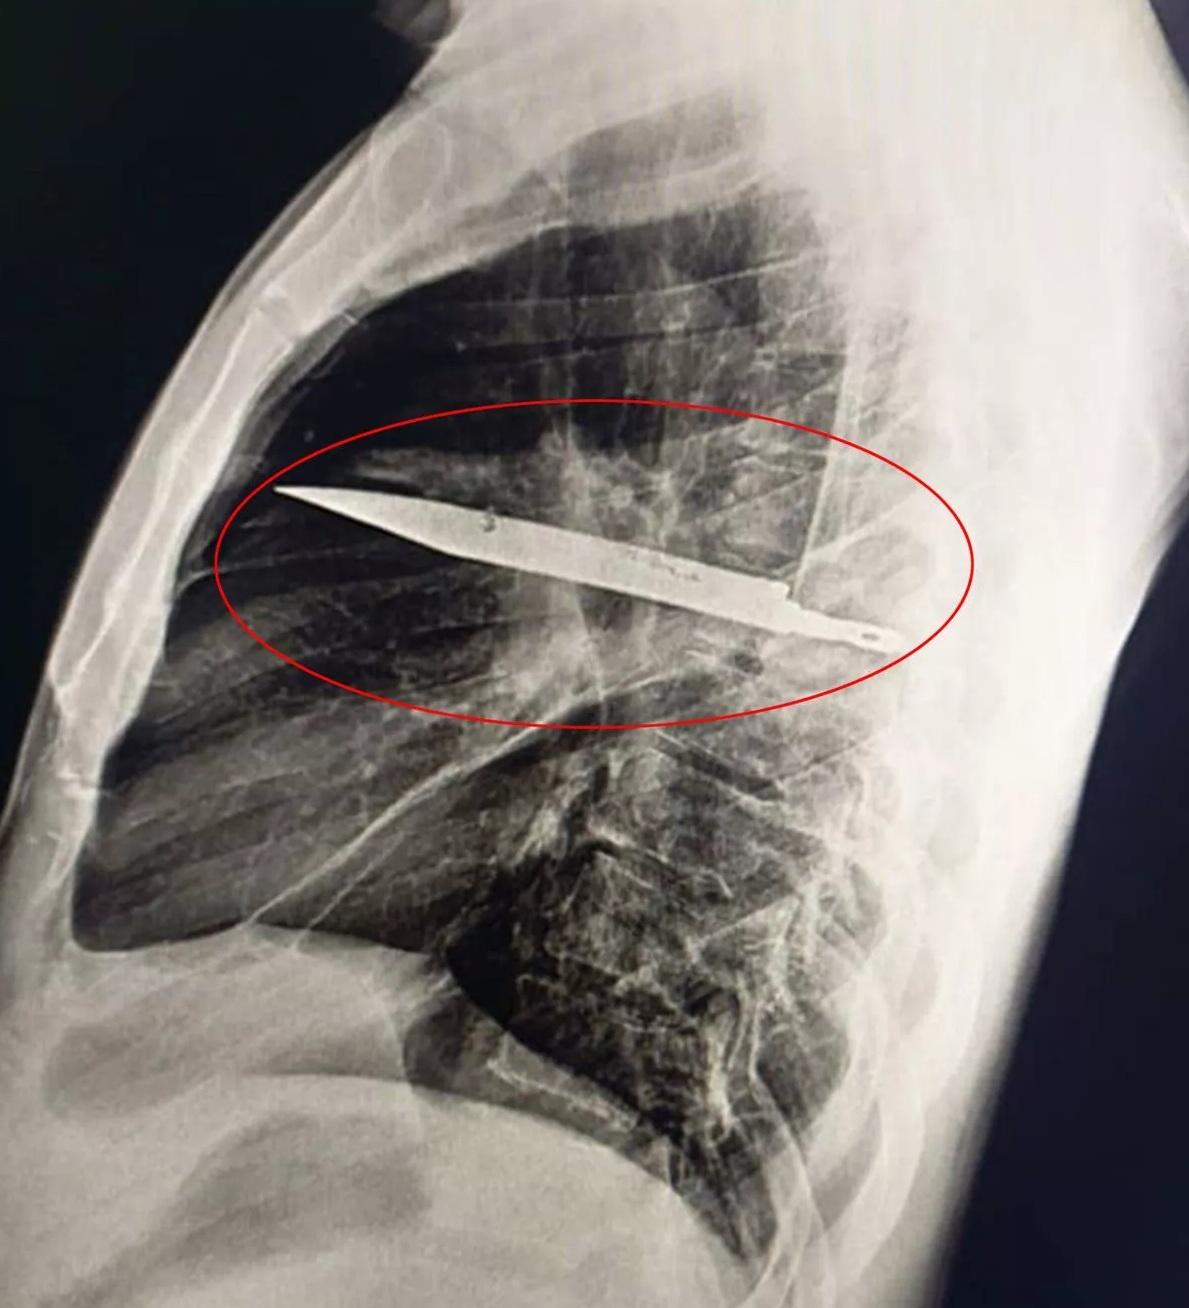

胸部X光影像可見,有一把刀插在男病人胸腔內。(互聯網)

胸部X光檢查結果顯示,有一把刀插在病人胸腔內。從X光影像可見,這把刀從右肩胛骨插入,奇蹟地避開重要器官。